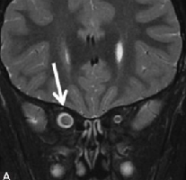

磁共振成像(MRI)是有用的迅速识别这些病理,以避免长期性视力丧失。在T2W图像上,显示中央等强度,周围高强度对应于神经周围蛛网膜神经胶质瘤。图3:NF1患者视神经胶质瘤。图...